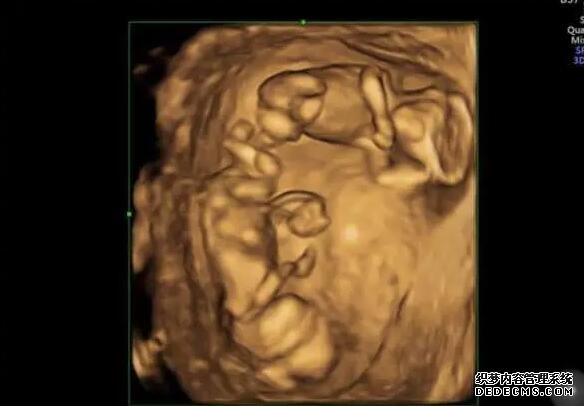

• 试管移植是一种辅助生殖技术,是许多不能自然怀孕的夫妻选择的方法。在试管移植过程中,女性需要注射人工促排卵药物来促进卵巢排卵。而在移植当天,打一针促黄体生成素能够帮助维持黄体功能,增加着床成功率,从而提高受孕率。